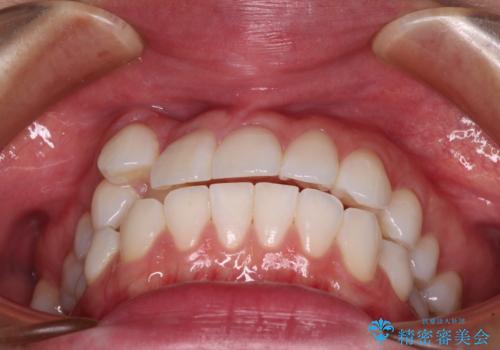

奥歯の咬み合わせを維持しながら正中位置を改善するために、補助装置を使用しました。

予定より期間がかかりましたが、上下の正中位置を綺麗に一致させることができました。